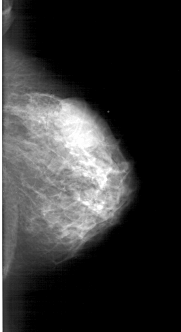

A_1803_1.RIGHT_CC

RIGHT_MLO LINES 6016 PIXELS_PER_LINE 3076 BITS_PER_PIXEL 12 RESOLUTION 43.5 NON_OVERLAY